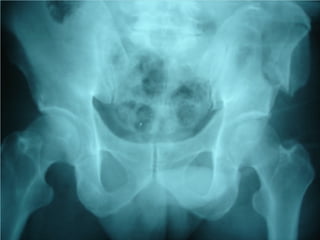

Fracture Pelvis

Associated injuries :

Head injury 51%

Extremity fracture 48%

Abdominal injury 28%

Peripheral nerve injury 26%

KUB injury 23%

Chest injury 22%

High mortality and morbidity rate

* 39% from hemorrhage

* 31% from associated injuries

* 30% from complications

Causes : traffic accident 84%

: falling from height 9%

: others 7%

Anatomy

Volume of Pelvis : ¶H( R² + 2Rr + r² )/3

R or r ↑ 2cm → vol. ↑ 1.3 litre

R or r ↑ 5cm → vol. ↑ 5.0 litre

Diagnosis

1. History of injury

* car accident

* motorcycle accident

* pedestrian accident

* falling from height

* crush injury

2. Physical examination

* marks at pelvis and perineum

* leg deformity or length discrepancy

* signs of ruptured urethra or bladder

* anorectal or vaginal lacerations

* pelvic compression test ???

3. Investigations

* pelvic film : AP , Inlet , Outlet , Judet

* FAST

* DPL

* CT scan

* Angiography